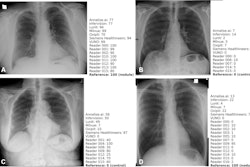

Human-AI symbiosis – rather than totally autonomous AI – should be the current goal for AI in chest radiography, according to an editorial published January 23 in Radiology.

Ultimately, AI algorithms have already been developed that can autonomously detect chest radiograph findings better human radiologists, the authors wrote. These results have been so impressive that some question whether AI will replace humans altogether, they noted.